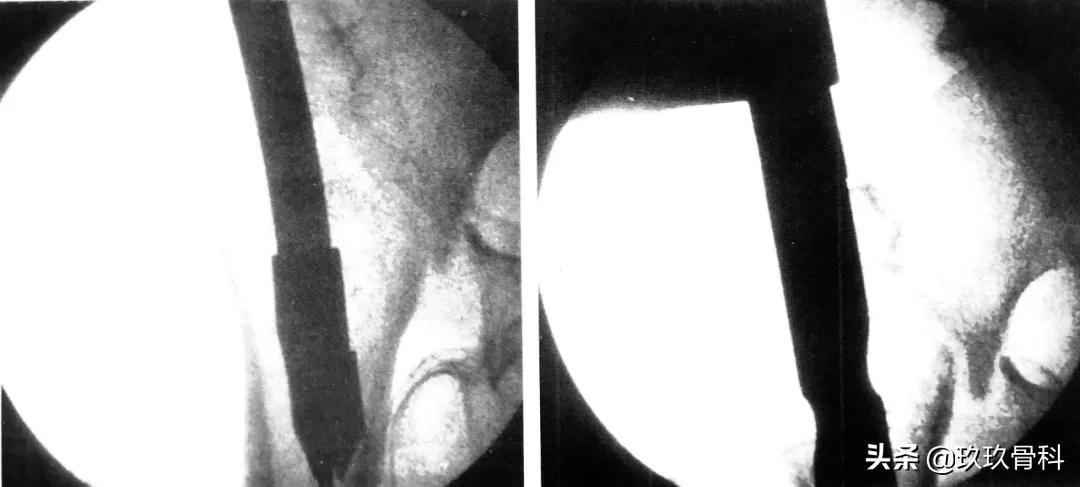

而逆行穿钉的入钉点位于肱骨远端后方,恰在尺骨鹰嘴窝近端。适用于肱骨远端1/3及中 1/3 骨折。该入路虽然避免了肩部冋题,但可造成肘部并发症,甚至在入钉点处发生医源性骨折,同时,受入路限制,只能使用直径较细的髓内钉。

肱骨逆行髓内钉,左图为入钉口置备,右图为穿入多根弹性髓内钉